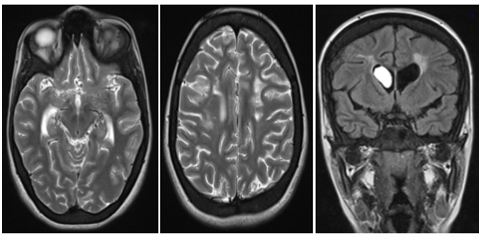

Case N°2

This is a 16-year-old girl, followed for sickle cell anemia since the age of 2years, having an antecedent DALY at 5years of age; who presented a brutal presentation of alertness disorder with right hemicopra deficiency related to left posterior cerebral AVCI. An MRI performed urgently in the three planes of space in weighted sequences T1, T2 FLAIR and angio-RM arterial. It highlights an AVCI range of different age in the most recent is left carotid. The ARM shows the interruption of the two internal carotids at the level of their terminal segment C1, which are of reduced caliber in their intracavalous path with no individualization of the proximal segments of the 2 anterior and posterior cerebral arteries, a fine anastomotic network at the base "pseudomoya" Figure 3 & 4.

Figure 3 Angioplasty MRI performed in emergency: in the 3 planes of space in T1, T2, FLAIR and arterial angio-RM: Presence of multiple bilateral hemispherical lesional foci of cortico-subcortical topography in hyper signal T2 and FLAIR , hypo-signal diffusion in the frontal bilateral, parieto-rollodial right and associated with signal abnormalities of the white matter under cortical and gray nuclei bilaterally of chronic vascular pace.with the presence of a beach lesional temporo-parieto-occipital left in hyper signal T2, FLAIR and diffusion b1000, erasing the cortical furrows with mass effect on the occipital intersection.

Figure 4 Arterial Angio-MRI: Interruption of the two internal carotid arteries in their C1 end segment, which are of reduced caliber in their intracavalous pathway with absence of individualization of the proximal segments of the 2 anterior and posterior cerebral arteries with evidence of a fine network at the "pseudomoya" base.